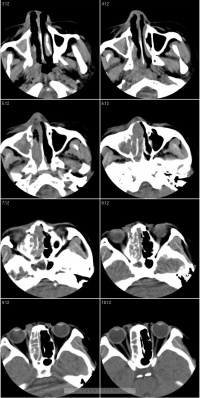

慢性鼻窦炎

慢性鼻窦炎,亦称慢性化脓性鼻窦炎。常因急性化脓性鼻窦炎反复发作未能得到适当治疗所致。以多粘液或脓性鼻涕、鼻塞头痛嗅觉减退或消失为主要临床症状。现代西医学除穿刺冲洗、手术疗法外,尚无理想的治疗措施。